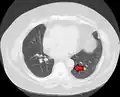

Mediastinal lipomatosis -

Mediastinal lipomatosis